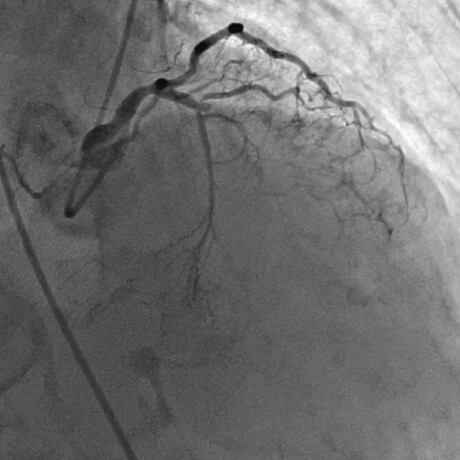

薬剤溶出性ステントを拡張中

治療後最終の造影